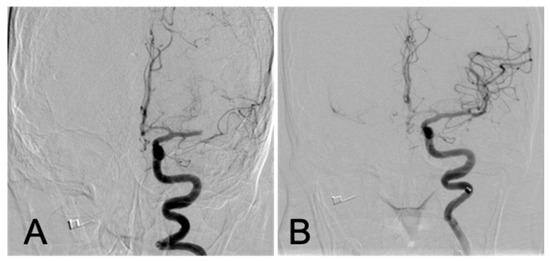

2. The Case